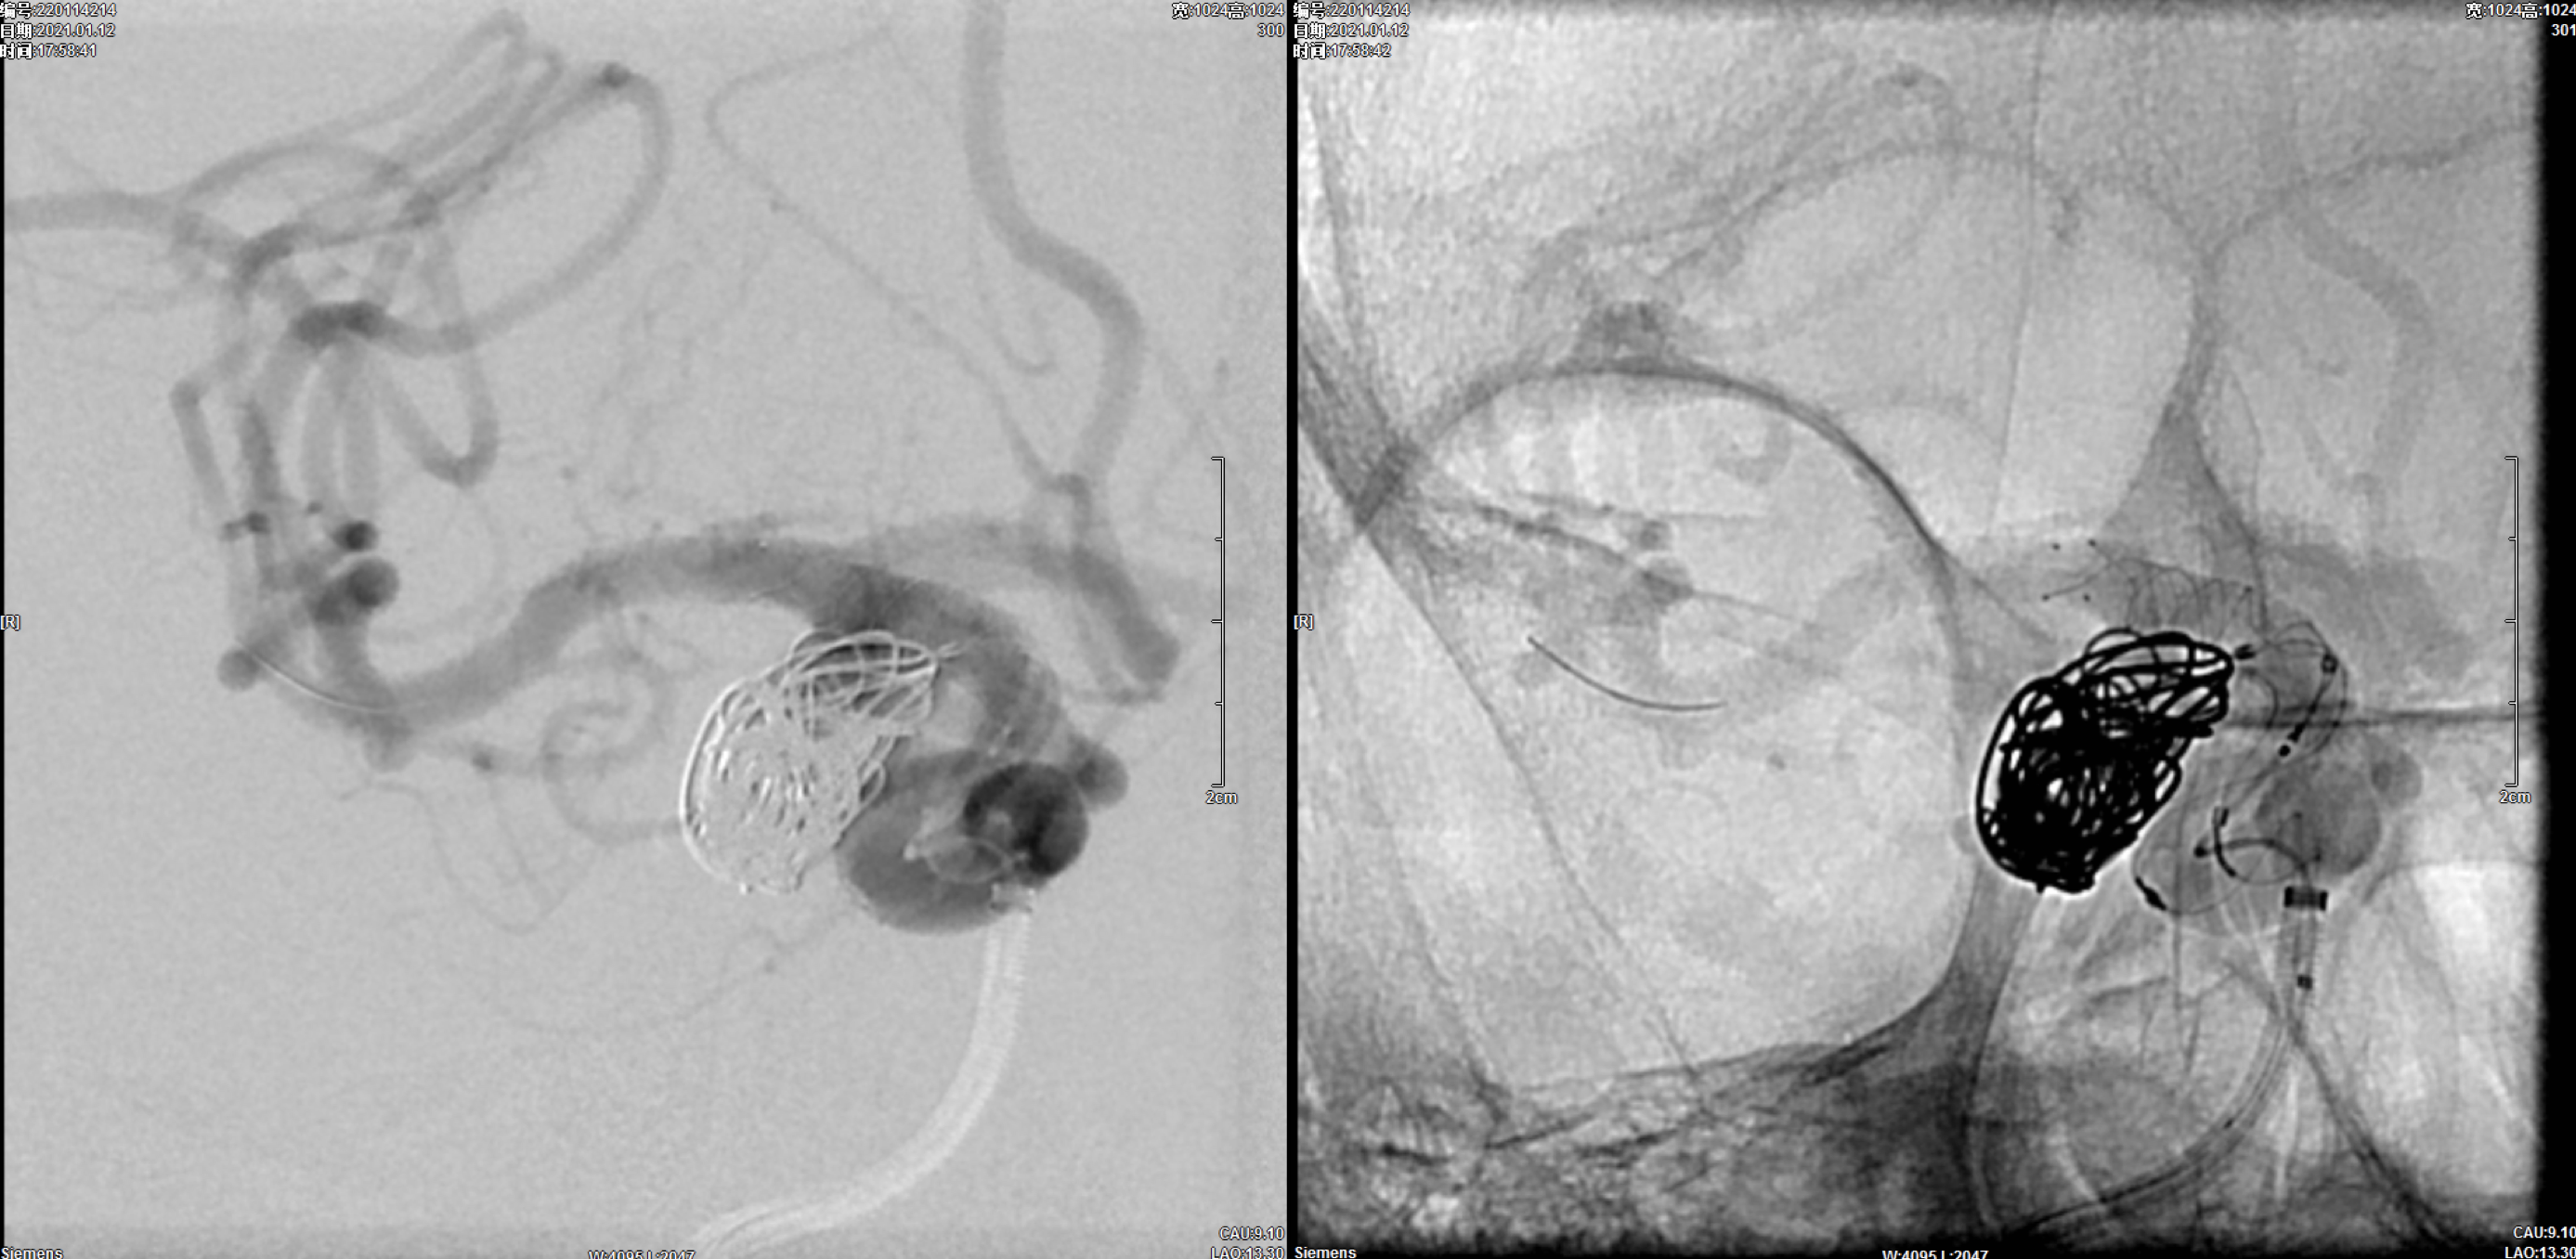

选择Lvis3.5mm*20mm支架半释放保护下经瘤腔深部栓塞微导管送入第一枚16mm*52cm弹簧圈后,经另一根栓塞微导管交替分区填塞动脉瘤瘤体!

完全释放支架后,处理瘤颈部!共送入9枚栓塞弹簧圈!

术后即刻正位造影:动脉瘤栓塞满意!

术后即刻侧位造影:动脉瘤栓塞满意!